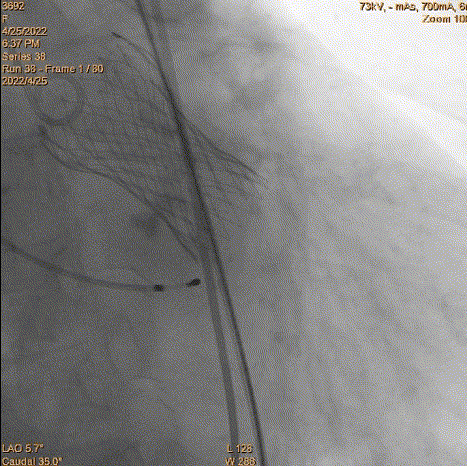

3、球囊预扩:由于钙化严重球囊无法通过,遂使用圈套器抓捕球囊。

套圈器抓球囊过瓣

20mm球囊预扩

导丝位置改变

对侧上圈套器准备